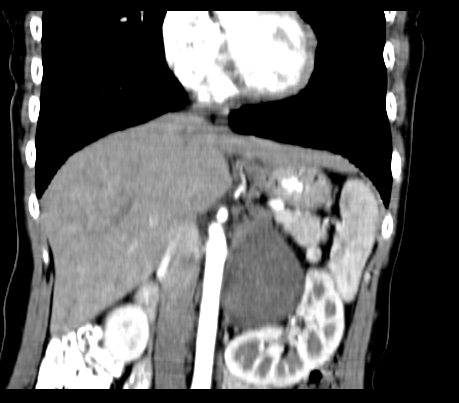

重建

腹部平扫

动脉期

静脉期